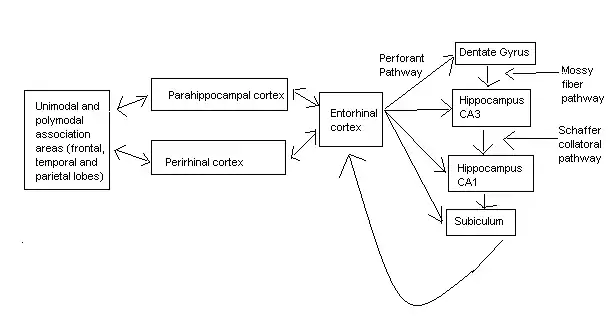

Psychologists and neuroscientists dispute over the precise role of the hippocampus, but, generally, agree that it plays an essential role in the formation of new memories about experienced events (Episodic or Autobiographical Memory).

Some researchers prefer to consider the hippocampus as part of a larger medial temporal lobe memory system responsible for general declarative memory (memories that can be explicitly verbalized — these would include, for example, memory for facts in addition to episodic memory). Some evidence supports the idea that, although these forms of memory often last a lifetime, the hippocampus ceases to play a crucial role in the retention of the memory after a period of consolidation. Damage to the hippocampus usually results in profound difficulties in forming new memories (anterograde amnesia), and normally also affects access to memories prior to the damage (retrograde amnesia). Although the retrograde effect normally extends some years prior to the brain damage, in some cases older memories remain intact - this sparing of older memories leads to the idea that consolidation over time involves the transfer of memories out of the hippocampus to other parts of the brain. However, researchers have difficulties in testing the sparing of older memories and, in some cases of retrograde amnesia, the sparing appears to affect memories formed decades before the damage to the hippocampus occurred, so its role in maintaining these older memories remains controversial.

Amnesia can occur when there is damage to a number of regions in the medial temporal lobe and their surrounding structures. The patient H.M. is probably one of the best known patients who suffered from amnesia. Removing his medial temporal lobes, including the hippocampus, seemed to be a good way to treat the epilepsy. What could be observed after this surgery was that H.M. was no longer able to remember things which happened after his 16th birthday, which was 11 years before the surgery. So given the definitions above one can say that he suffered retrograde amnesia. Unfortunately, he was not able to learn new information due to the fact that his hippocampus was also removed. H.M. therefore suffered not only from retrograde amnesia, but also from anterograde amnesia. His Implicit Memory, however, was still working. In procedural memory tests, for example, he still performed well. When he was asked to draw a star on a piece of paper which was shown to him in a mirror, he performed as bad as every other participant in the beginning. But after some weeks his performance improved even though he could not remember having done the task many times before. Thus, H.M.’s Declarative Memory showed severe deficits but his Implicit Memory was still fine. Another quite common cause of amnesia is the Korsakoff’s syndrome or also called Korsakoff’s amnesia. Long term alcoholism usually elicits this Korsakoff’s amnesia due to a prolonged deficiency of vitamin B1. This syndrome is associated with the pathology of the midline diencephalon including the dorsomedial thalamus. Alzheimer’s disease is probably the best known type of amnesia because it is the most common type in our society. Over 40 percent of the people who are older than 80 are affected by Alzheimer’s disease. It is a neurodegenerative disease and the region in the brain which is most affected is the entorhinal cortex. This cortex forms the main input and output of the hippocampus and so damages here are mostly severe. Knowing that the hippocampus is especially involved in forming new memories one can already guess the patients have difficulties in learning new information. But in late stages of Alzheimer’s disease also retrograde amnesia and even other cognitive abilities, which we are not going to discuss here, might occur.